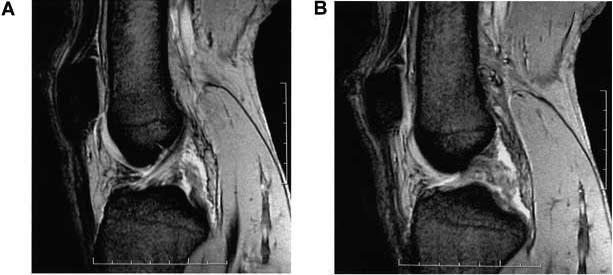

18歳の男性。サッカーの試合中に方向転換しようとして膝関節をひねり、疼痛のため歩行不能となった。翌日に撮像したMRIを示す。この患者で認められないのはどれか。

O3_d7x0jj4z6CSn0aDWC1

1

膝蓋跳動

2

Nテスト陽性

3

前方引き出し徴候

4

後方引き出し徴候

5

ラックマンテスト陽性

18歳の男性。サッカーの試合中に方向転換しようとして膝関節をひねり、疼痛のため歩行不能となった。翌日に撮像したMRIを示す。2週後に歩行可能となったが、膝関節に不安定感がある。適応となる装具はどれか。

7e8wUVAbF6dnJTnYT6XlS